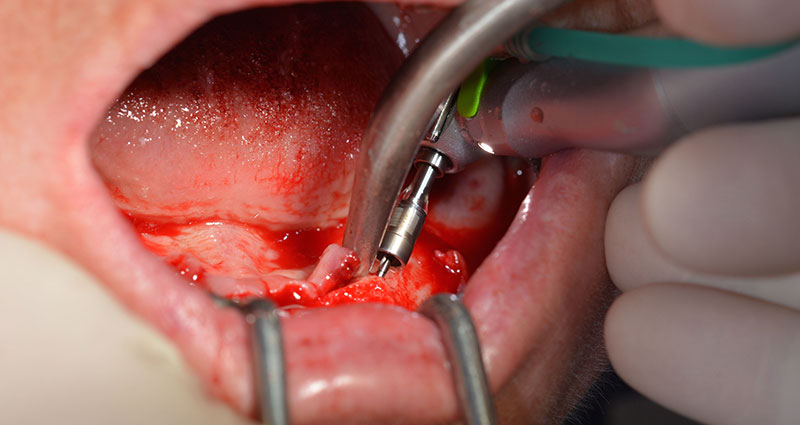

Il prossimo passaggio programmato prevede ancora il posizionamento degli impianti. Solitamente, in questa fase il nostro studio utilizza una coppia di 32 Ncm (Fig. 12 e 13).

L'alta solidità è un requisito indispensabile per una ricostruzione immediata. Per garantirla, in questo caso il foro non è stato filettato. L'unità di perforazione Implantmed di W&H è dotata di una modalità speciale per questo scopo, che può essere selezionata direttamente ed è indispensabile in molte situazioni. In fase di posizionamento degli impianti, i giri finali hanno superato il valore di 32 Ncm e sono stati terminati a mano. In questi casi, consigliamo l'utilizzo della funzione autofilettante del sistema di implantologia e la rotazione degli impianti all'indietro e in avanti, per diverse volte. Questo permette all'impianto di assumere gradualmente la posizione finale, evitando un'eccessiva pressione all'osso (Fig. 14).